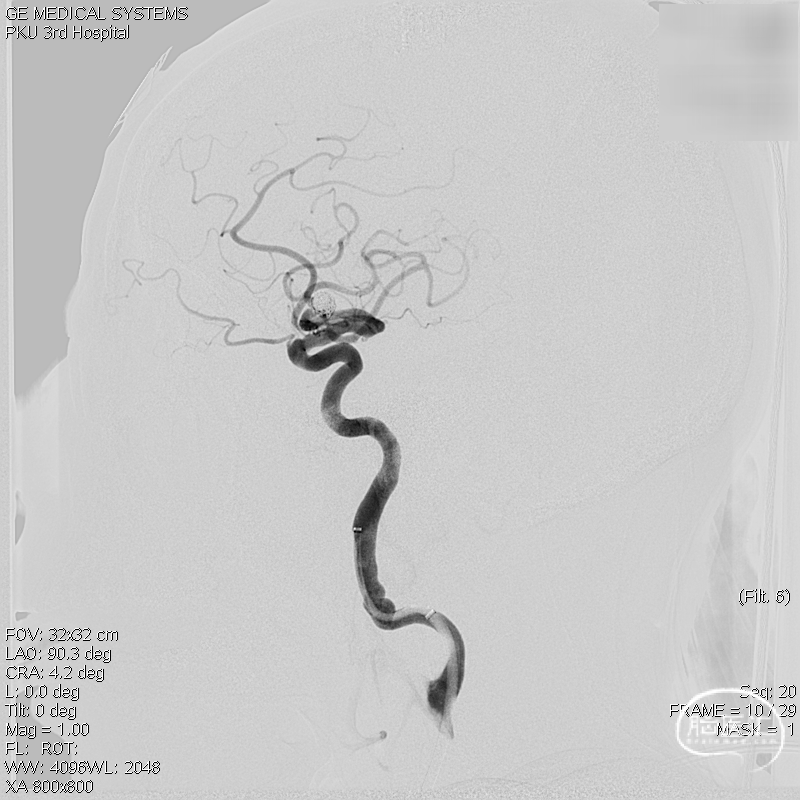

术前影像学检查:术前正侧位。

术前工作位与三维重建:显示右侧MCA分叉部未破裂动脉瘤,6.9mm*7.2mm,瘤颈7.4mm。该病例之困难在于M1迂曲成袢。

复查标准正侧位造影, ICA、MCA、ACA主干及远端分支良好,动脉瘤栓塞满意。

术后工作位+侧位造影